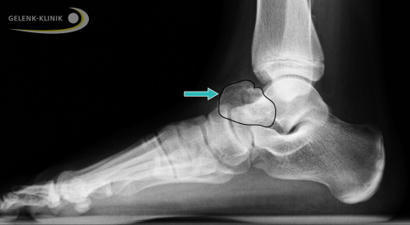

Die kartilaginäre Exostose am Fuß und Sprunggelenk ist ein gutartiger Knochentumor. Die kartilaginäre Exostose wird auch als Osteochondrom bezeichnet. Die Exostose besteht aus langsam verknöcherndem Knorpel und Knochengewebe. Dieses Osteochondrom kann praktisch an allen Knochen als gutartige Wucherung der Epiphysenfuge (Wachstumszone) des Körpers vorkommen. Learn more / En savoir plus / Mehr erfahren: https://www.scoop.it/topic/21st-century-innovative-technologies-and-developments/?&tag=Health